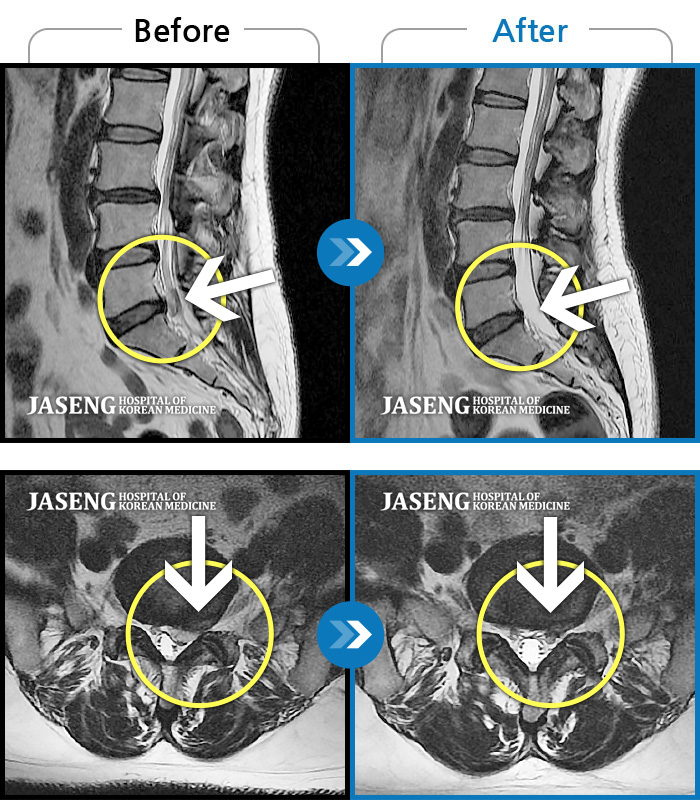

ȯںп Ǹ ǿ ԿǾ, ο ġ ۿ Ƿ ġḦ Ͻñ ٶϴ.